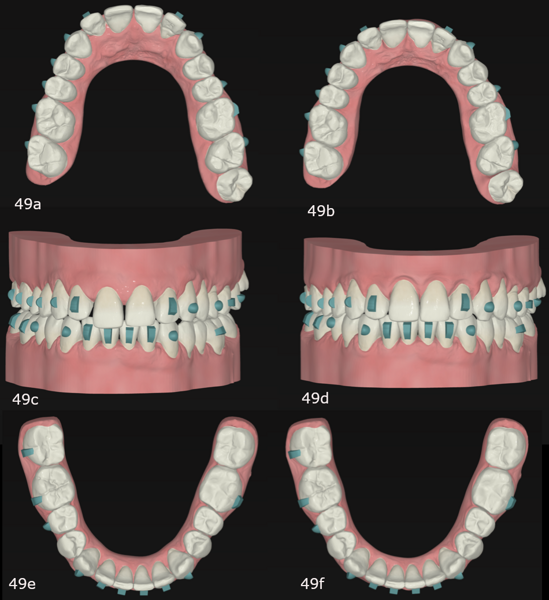

Figs. 9a–f: (a) Frontal view. (b) Overjet view. (c) Left lateral view. (d) Upper oclussal view. (e) Right lateral view. (f) Lower oclussal view.

Initial treatment in 29 stages was planned, by which point the final occlusal results would have been obtained. We began with the placement of attachments and micro-screws in the maxillary arch for posterior intrusion (Fig. 18). After seven months of treatment and in the 20th stage, we introduced the FAS STOP and GO concept and took new records to prepare for the second phase of aligner treatment (Fig. 19). Thanks to STOP and GO, it is possible to achieve better tracking so that aligners fit properly and shorter treatment times using fewer aligners. This is the advantage of planning in different stages. It helps us achieve all our treatment goals on a consistent basis, and treatment efficiency is much higher.

The second phase of treatment began with the placement of new attachments (Figs. 20–22) and consisted of 12 stages, during which we continued to intrude the maxillary molars, centre the mandibular midline and level the occlusal planes. This phase lasted for four months. The total treatment involved 32 stages over 11 months, and all the treatment goals were achieved (Figs. 23–25).